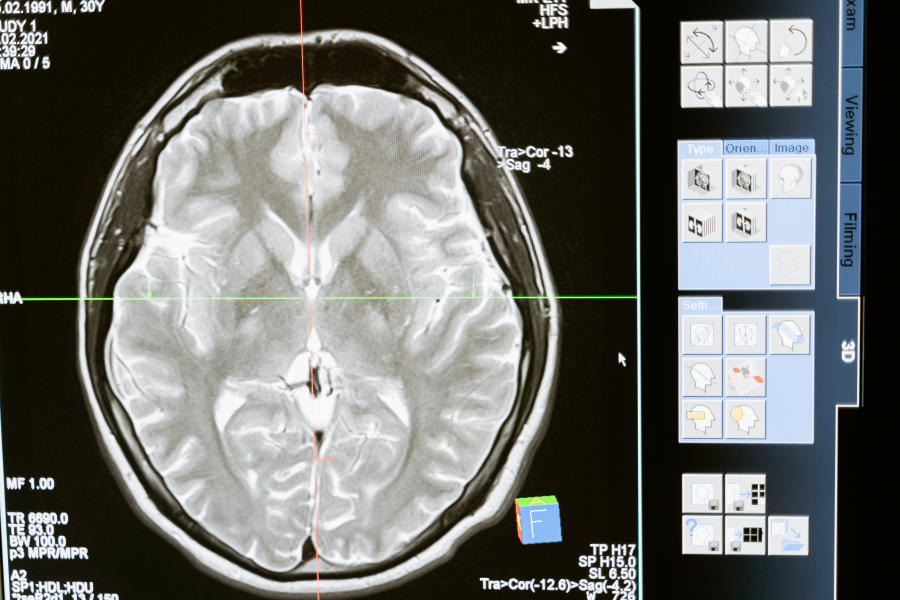

Παρουσίασαν επίσης χαμηλότερες ταχύτητες επεξεργασίας, γεγονός που ευθυγραμμίζεται με προηγούμενες παρατηρήσεις μετά το COVID-19 για μειωμένη κατανάλωση γλυκόζης στον εγκέφαλο εντός του μετωποπαρεγκεφαλιδικού δικτύου του εγκεφάλου, το οποίο είναι υπεύθυνο για την προσοχή, την επίλυση σύνθετων προβλημάτων και τη μνήμη εργασίας, μεταξύ άλλων λειτουργιών.

Υπάρχουν διάφοροι παράγοντες που θα μπορούσαν να προκαλέσουν τα γνωστικά ελλείμματα, λένε οι ερευνητές. Η άμεση ιογενής λοίμωξη είναι πιθανή, αλλά είναι απίθανο να αποτελεί σημαντική αιτία- αντίθετα, είναι πιο πιθανό να συμβάλλει ένας συνδυασμός παραγόντων, όπως η ανεπαρκής παροχή οξυγόνου ή αίματος στον εγκέφαλο, η απόφραξη μεγάλων ή μικρών αιμοφόρων αγγείων λόγω θρόμβωσης και οι μικροσκοπικές αιμορραγίες.

Ωστόσο, τα αναδυόμενα στοιχεία δείχνουν ότι ο σημαντικότερος μηχανισμός μπορεί να είναι η βλάβη που προκαλείται από τη φλεγμονώδη αντίδραση και το ανοσοποιητικό σύστημα του ίδιου του οργανισμού.

Ο καθηγητής Menon και ο καθηγητής Ed Bullmore από το Τμήμα Ψυχιατρικής του Cambridge είναι συν-επικεφαλής ομάδων εργασίας στο πλαίσιο της κλινικής μελέτης νευροεπιστήμης COVID-19 (COVID-CNS), οι οποίες στοχεύουν στον εντοπισμό βιοδεικτών που σχετίζονται με τις νευρολογικές διαταραχές ως αποτέλεσμα του COVID-19, καθώς και των νευροαπεικονιστικών αλλαγών που σχετίζονται με αυτές.